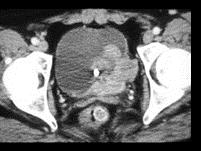

男,56岁,间歇性血尿半年余,请根据所示图像,选择最可能诊断 ( )A、膀胱癌B、膀胱息肉C、膀胱血块D、膀胱结核E、膀胱结石

问题 男,56岁,间歇性血尿半年余,请根据所示图像,选择最可能诊断 ( )

选项 A、膀胱癌 B、膀胱息肉 C、膀胱血块 D、膀胱结核 E、膀胱结石

答案 A